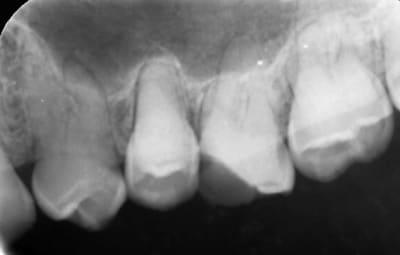

Radio 11

8af24b3d fd05 4021 a759 7a5e9e05a6a7 h5jlk1 - Eugenol

poignée de porte a diagnostiqué une maladie genetique, c'est un cas d'amélogenèse imparfaite avec racines courtes, obliteration des chambres pulpaires, émail fin et de mauvaise minéralité pour du collage... necrose en lien avec l'usure (les incisives inf)

il faudrait donc faire des élongations maousses , mais comme les racines sont courtes , ce sera des implants .